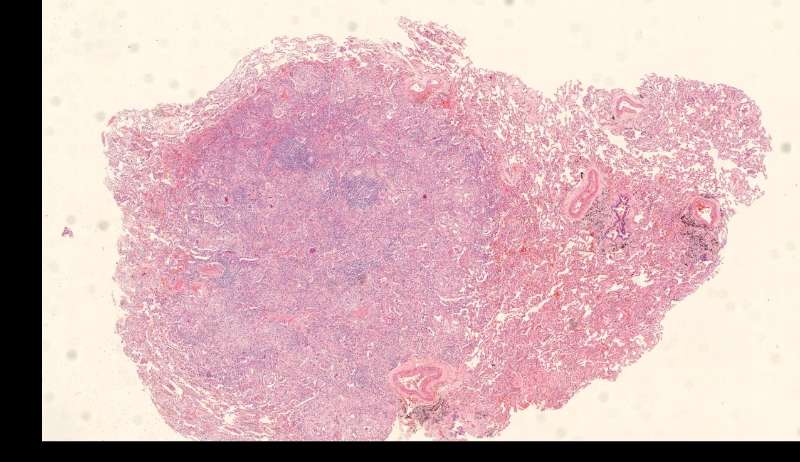

整体是个类圆形,边界模糊(有晕征的感觉),肉芽肿一般都这样 里面也能见到许多小白球,大小从3微米到20微米不等 红细胞直径5-6微米 普通小淋巴细胞直径5微米 这里淋巴细胞挺多 有许多淋巴细胞,成堆

多核巨噬细胞吞了许多隐球菌 经常是反包围的感觉

这三幅是周围区,也有巨噬细胞,单核的多 都在肺泡腔内 所以有ggo样密度 过一段时间,晕就消失,有时是消退,有时是实性区扩大,盖住磨玻璃晕 那也是吞噬的作用,常代表免疫力正常 就是警察多了把肺泡填了